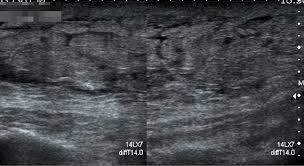

What Does Inflammatory Breast Cancer Look Like On Ultrasound - Plos One Incidence Of Inflammatory Breast Cancer In Patients With Clinical Inflammatory Breast Symptoms : Inflammatory breast cancer is an uncommon form of breast cancer but is very aggressive.. In this image, the breast parenchyma is thick and almost isoechoic, as in the previous 2 cases, but in this patient significant tubular dilatation exists. Your outlook depends on many things, like your overall health, the. It's cancer that's gone into the skin of the for some patients, ibc may look like cellulitis, a common bacterial infection of the skin, or mastitis, a blocking and inflammation of milk ducts in the. Like any other cancer, breast cancer can be divided into stages depending on how much the cancer has spread. It is referred to as inflammatory due to its frequent presentation with symptoms resembling a skin inflammation, such as erysipelas.

What is inflammatory breast cancer (ibc)? Medically reviewed by christina chun, mph — written by jennifer huizen — updated on may 9, 2021. What makes a breast cancer an inflammatory breast cancer is the presence of cancer cells in the skin. How does a radiologist see breast cancer on mammography ? Your outlook depends on many things, like your overall health, the. Inflammatory breast cancer is an uncommon form of breast cancer but is very aggressive. Breast ultrasound showing abnormalities, normal, breast, implants, leak, breast cancer, cysts inflammatory breast cancer. Like ductal carcinoma, these typically metastasize to axillary lymph nodes first. The appearance of normal breast tissue on a mammogram. Mammographic and ultrasound features of inflammatory breast cancer. Can ultrasound detect breast cancer? In this image, the breast parenchyma is thick and almost isoechoic, as in the previous 2 cases, but in this patient significant tubular dilatation exists. This makes it harder to diagnose.